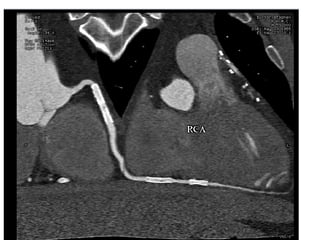

A 60-year-old male with multiple comorbid issues presented to the emergency room with chest pain. An ECG showed tall T waves and right bundle branch block. A CT/PET stress test revealed a small inferolateral infarct and significant peri-infarct ischemia. The patient was referred to cardiology to rule out acute coronary syndrome.